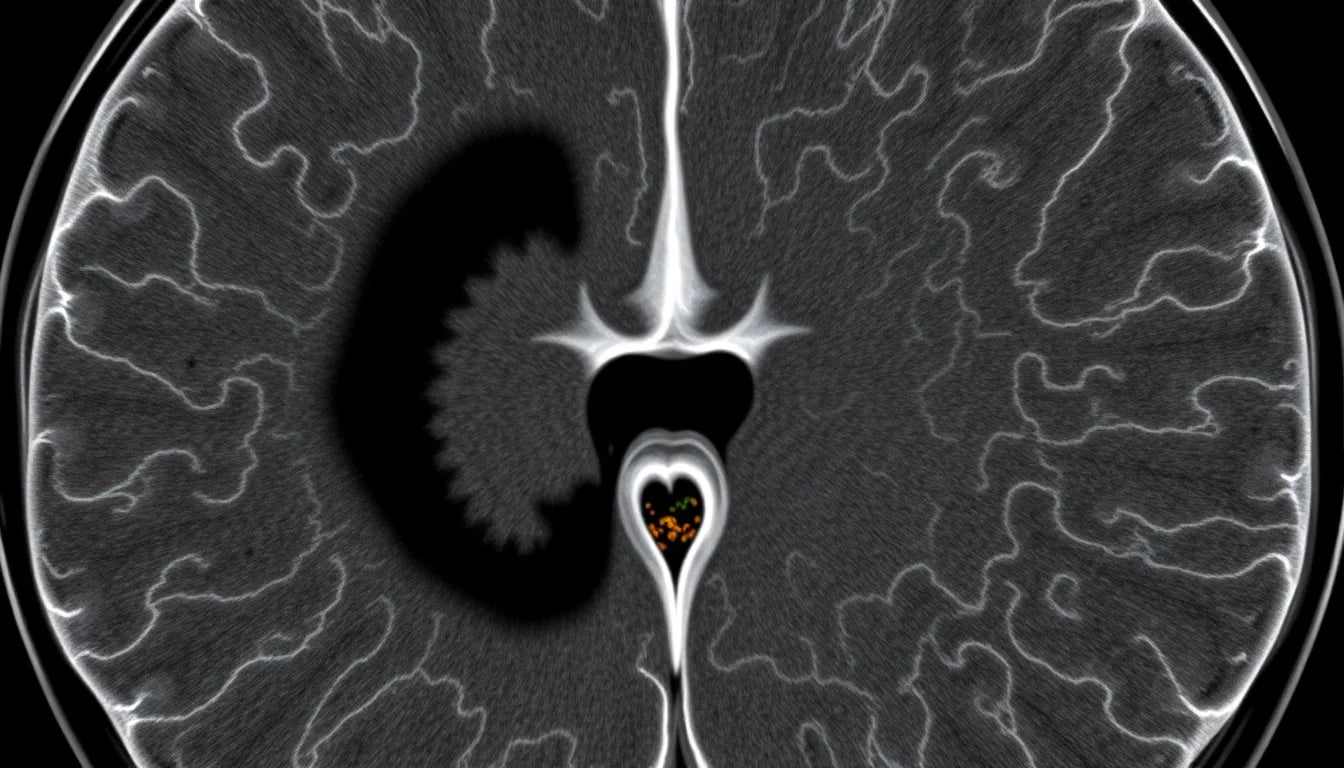

Accurate diagnosis is the cornerstone of effective management for a displaced disc in the jaw. The diagnostic process typically begins with a comprehensive clinical evaluation, where healthcare providers assess symptoms and jaw function. Imaging techniques, such as MRI or CT scans, may be employed to visualize the position of the disc and any associated structural abnormalities. These diagnostic tools help in tailoring a treatment plan that best suits the individual patient's needs.